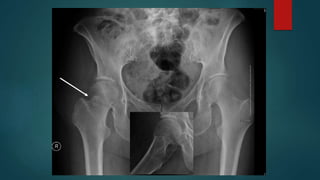

 Plain Film

 Consider traction-internal rotation view if

comminuted

 CT scan

 Displacement

 comminution

Diagnosis